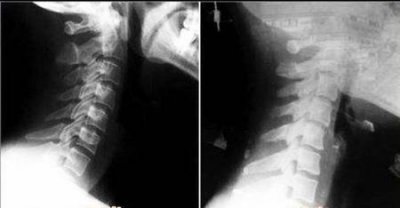

有颈椎病怎么睡觉比较好(颈椎病睡觉的正确睡姿) 颈椎病主要两个发病原因一个是长期久坐使用电脑手机,另一个就是睡姿问题。下图就是颈椎病生理曲度变直,和正常颈椎的x线图片。...